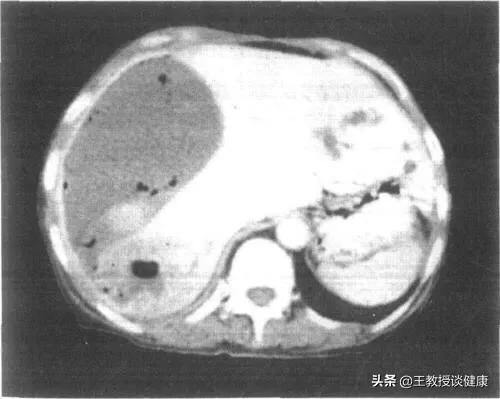

CT检查所见肝右叶肝脓肿影像